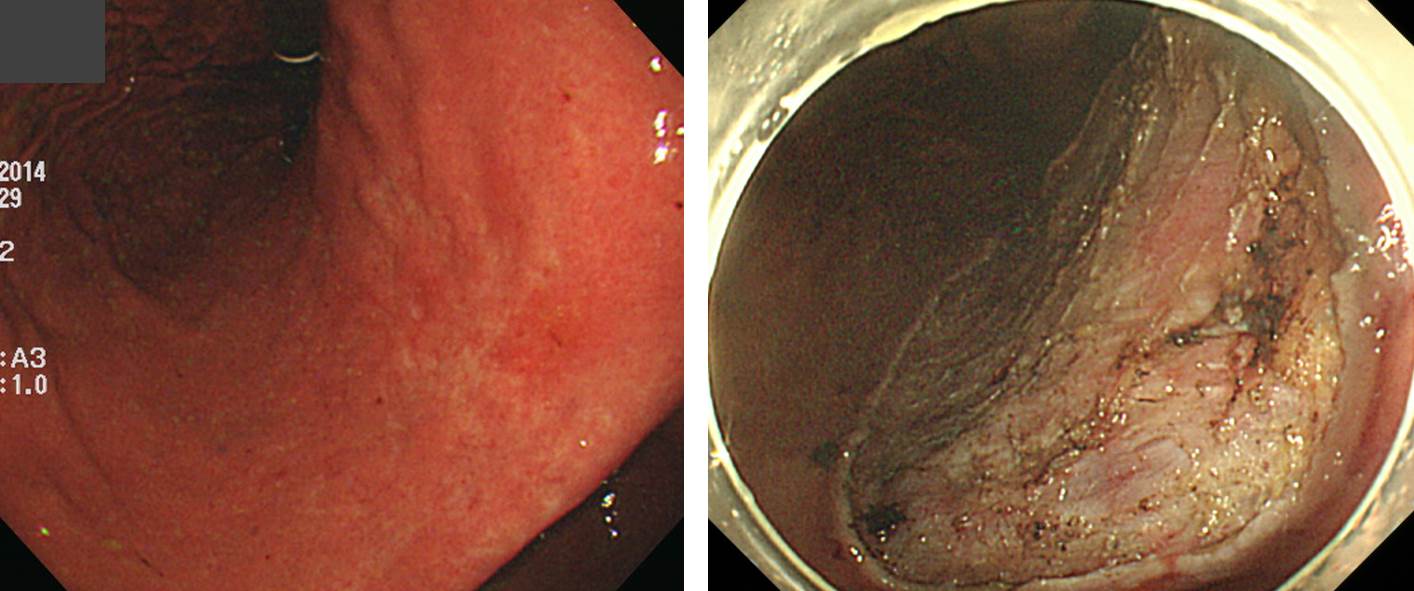

Á¶Á÷°Ë»ç°¡ atypical gland¿´°í ESD¸¦ ÇÏ¿© ÀÇ¿ÜÀÇ °á°ú°¡ ³ª¿Ô½À´Ï´Ù.

Early gastric carcinoma

1. Location : low body, lesser curvature

2. Gross type : EGC type IIc

3. Histologic type : lymphoepithelioma-like carcinoma

4. Histologic type by Lauren : intestinal

5. Size of carcinoma : (1) longest diameter, 5mm (2) vertical diameter, 4mm

6. Depth of invasion : invades mucosa (lamina propria) (pT1a)

7. Resection margin : free from carcinoma(N), safety margin : distal 23 mm, proximal 8 mm, anterior 16 mm, posterior 40 mm

8. Lymphatic invasion : not identified(N)

9. Venous invasion : not identified(N)

10. Perineural invasion : not identified(N)

11. Microscopic ulcer : absent

12. Histologic heterogeneity: absent